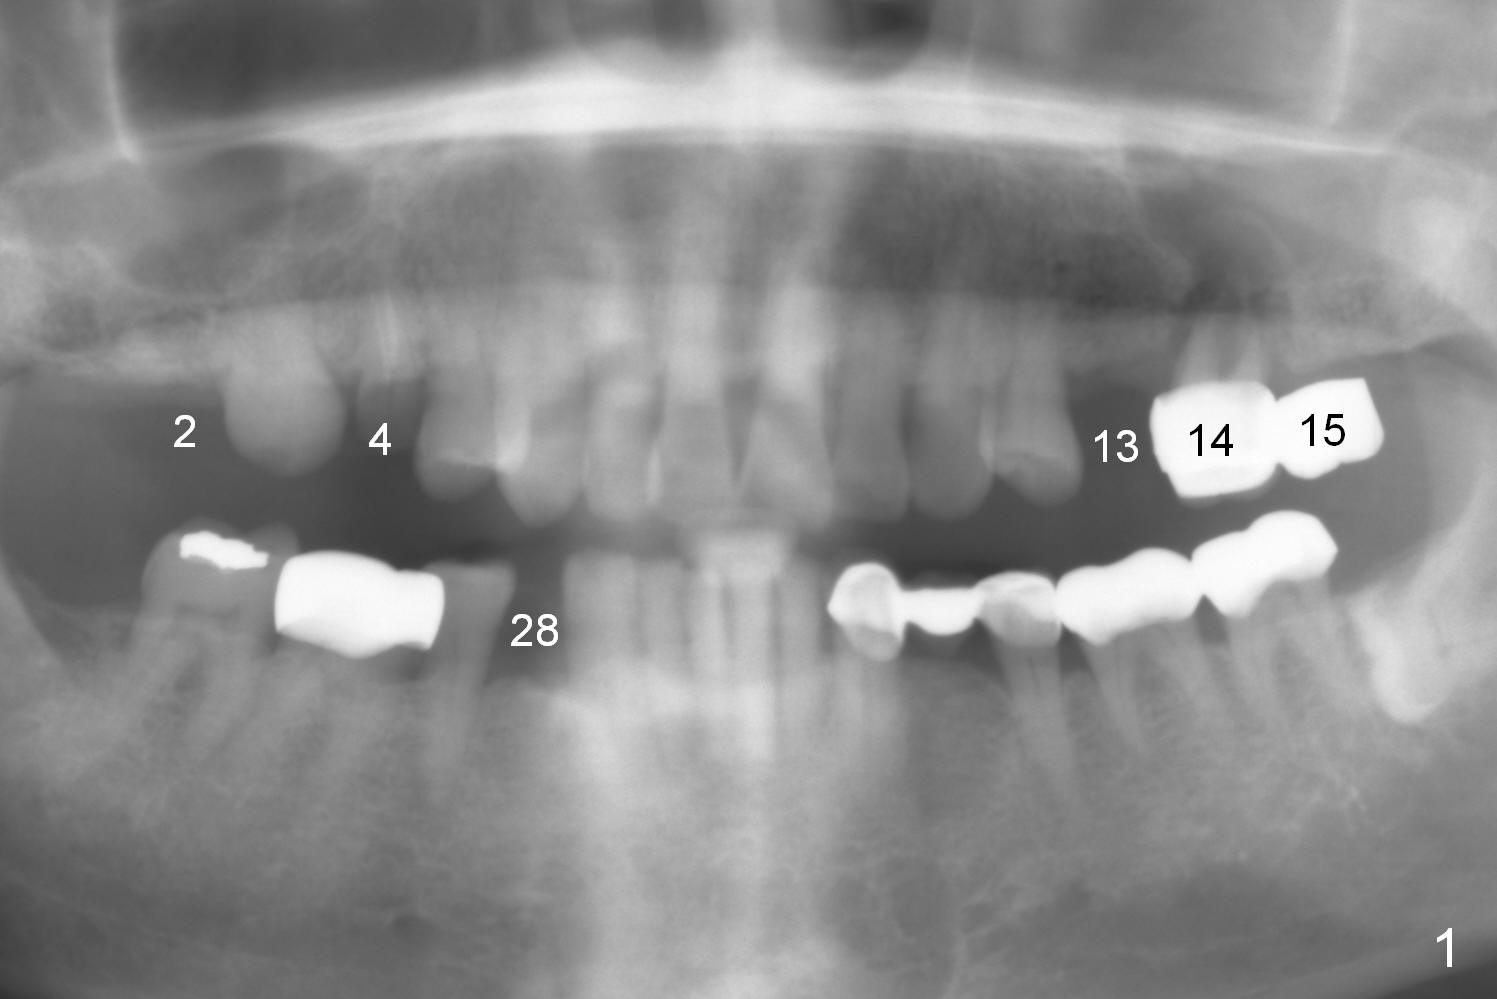

The 72-year-old man will return for #13-15 implantation after that at #2/4 and 28. There is severe wear in the cingula of the upper anterior teeth due to posterior collapse (several missing teeth, residual root and failing restoration, Fig.1). Prior to removal of the cantilever bridge (#14.15), an implant is placed at #13 (Fig.2). If the defect at #14 is too large after extraction, an implant is placed at #15 with an immediate provisional bridge (Fig.3 white line). Otherwise a large implant (possibly Tatum tapered) will be placed at #14 (Clindamycin) with splinted immediate provisional (Fig.4). Allograft is expected for sinus lift at #14 and 15 (Fig.3,4 red circles with Osteogen in 3:1 ratio). For socket preservation at #14, mix equal amount of allograft and Osteogen (Fig.3 pink), followed by Collagen plug (yellow) and the pontic of the provisional bridge. Prepare PRF (3-4 tubes of blood, one of them to be made for a plug).